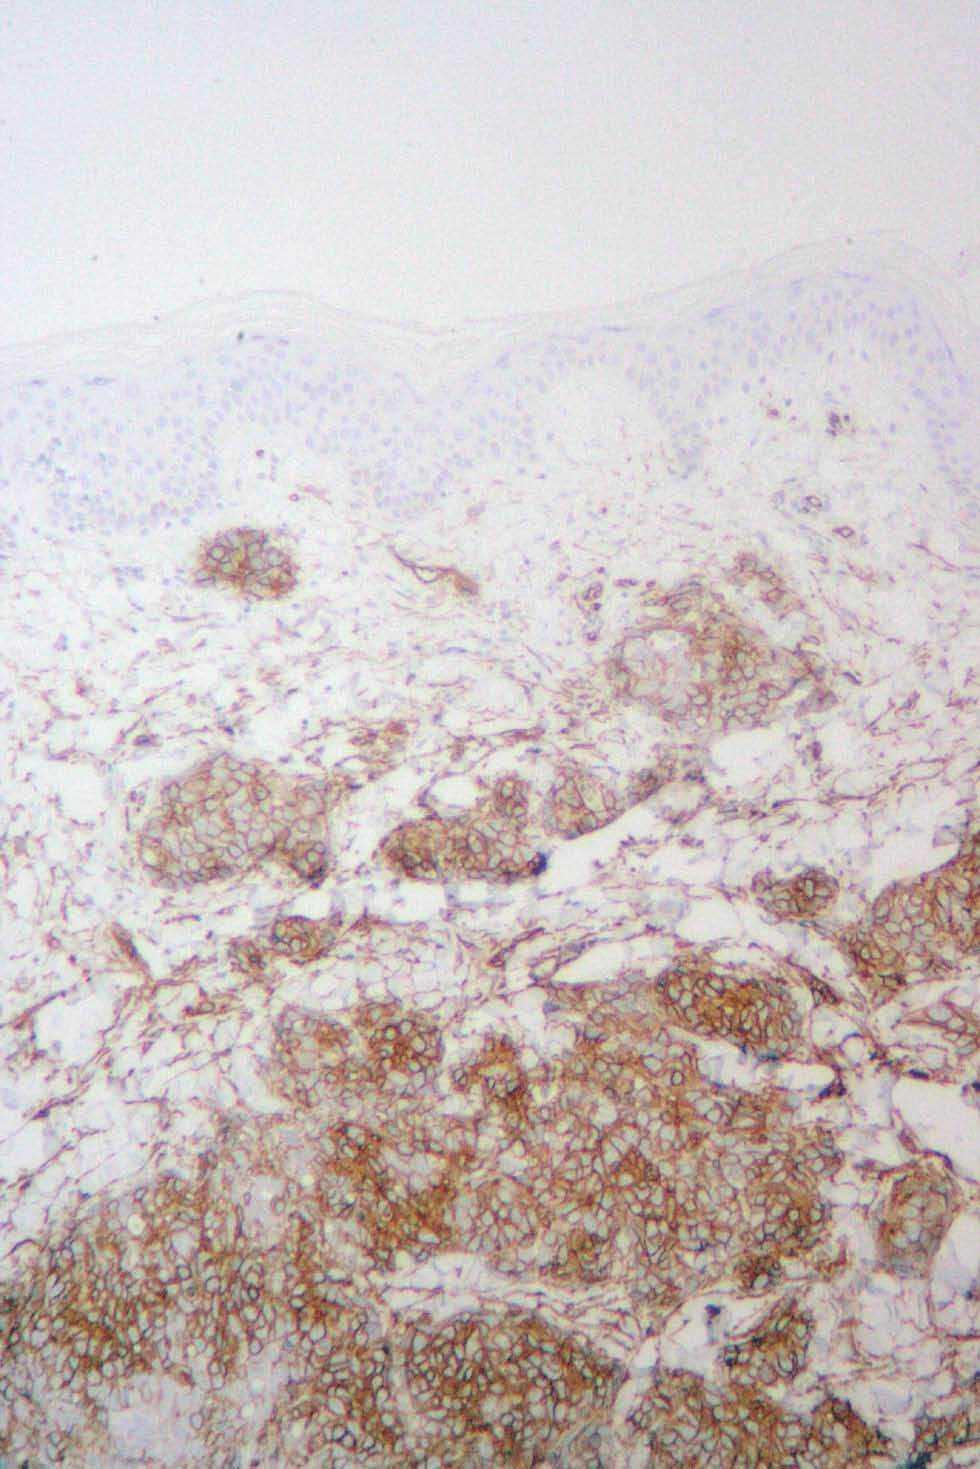

Varón de 42 años, intervenido a los 10 años de una lesión en la ingle derecha que el paciente definió como «lipoma» (no aportó informe anatomopatológico). A partir de dicha intervención desarrolló un aumento del diámetro de la extremidad inferior derecha (homolateral a la extirpación del lipoma), que se extendió al muslo y los genitales, siendo diagnosticado de linfedema secundario de miembro inferior derecho. Años después apareció una lesión eritematosa extensa y mal definida que abarcaba la mayor parte del territorio del linfedema, respetando pequeñas zonas como la raíz del muslo (figs. 2 y 3). En el diagnóstico histológico, la tinción de hematoxilina-eosina (fig. 4) mostraba pocas luces vasculares por tratarse de un angiosarcoma poco diferenciado. Por esta razón, el diagnóstico fue confirmado por las técnicas inmunohistoquímicas: citoqueratina negativa (que tiñe las células epiteliales, y por tanto esta neoplasia no está constituida por células derivadas del epitelio), vimentina positiva (que tiñe células tumorales) y CD34 positivo (este último marcador es diagnóstico, pues es específico del endotelio vascular del que deriva esta neoplasia) (fig. 5). Se realizó estudio de extensión (tomografía axial computarizada [TAC] toracoabdominal y resonancia magnética [RM] de miembro inferior derecho) que resultó negativo. Se inició un tratamiento con ifosfamida más adriamicina, recibiendo un total de cuatro ciclos. En la respuesta clínica se observó una disminución del edema y eritema. Se trató posteriormente con adriamicina liposomal con nula respuesta y desarrollando complicaciones como fenómenos isquémicos distales y sobreinfección. Debido a la mala evolución se decidió la amputación del miembro con desarticulación de la cadera e injerto en muñón. Actualmente se ha confirmado la progresión de la enfermedad con afectación cutánea, localizada en el flanco izquierdo y está recibiendo quimioterapia de segunda línea.

Fig. 5.--Técnicas de inmunohistoquímica: CD34 positivo. Muy específico del endotelio vascular del que deriva el angiosarcoma, marcaje que da el diagnóstico.